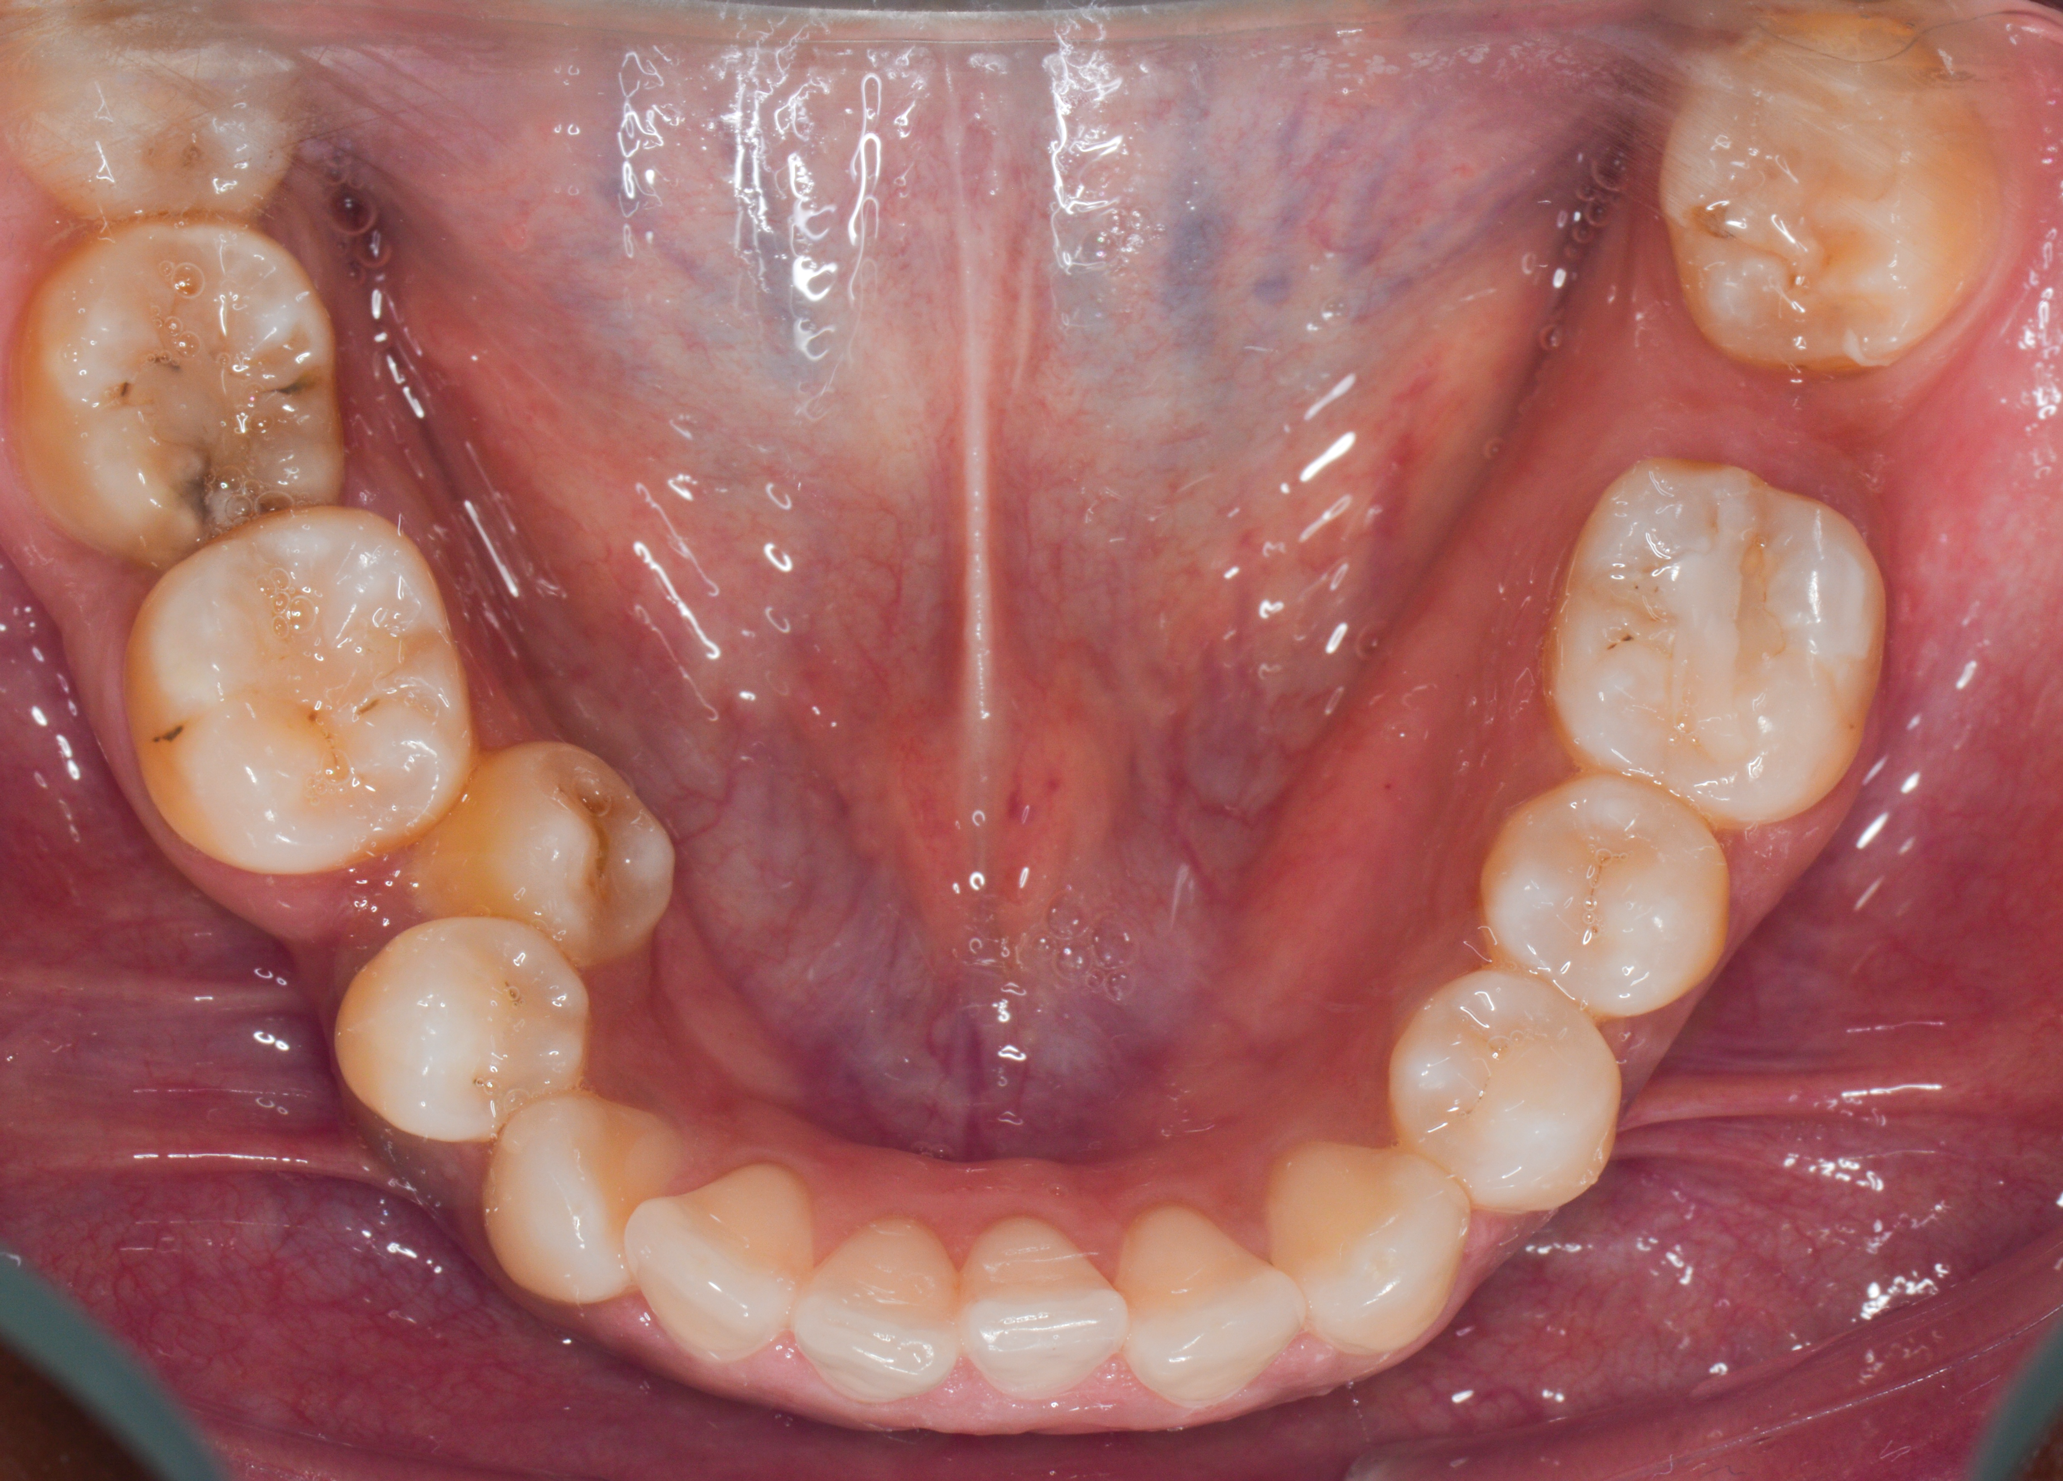

Fig 8. A class III adult male patient required surgical orthodontic treatment. The patient had anterior and posterior crossbites and required leveling of a deep curve of Spee during presurgical orthodontics.

Figure 8